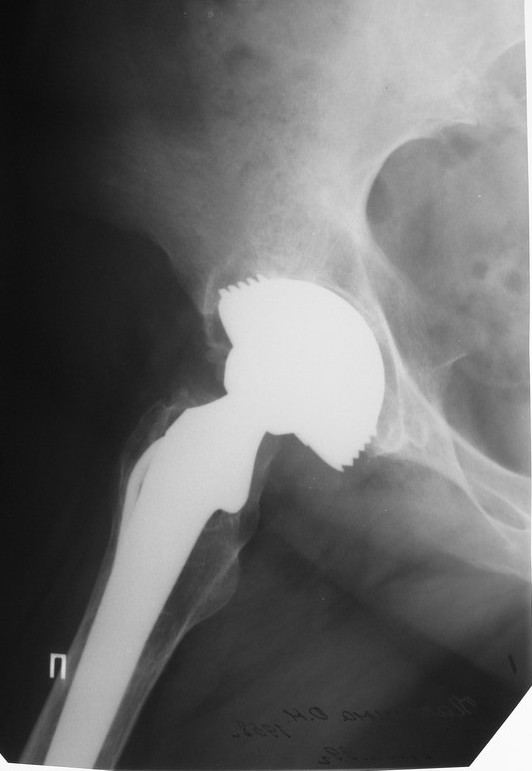

Уважаемые коллеги,в клинику поступила пациентка 51год с нестабильным антипротрузионным кольцом и вывихом эндопротеза. В течени длительного времени у пациентки ревматойдный полиартрит с приемом преднизолона. В 1994 году произведено эндопротезирование правого тазобедренного сустава бесцементным эндопротезом Biotronic. В 2000году по поводу нестабильности эндопротеза проведено ревизионное вмешательство-удаление чашки и ножки, некрэктомия. Установка антипротрузионного кольца, цементной чашки и ревизионной цементной ножки Beznoska. В 2007году выявлена клиникорентгенологическая картина нестабильности кольца. В 2008году пациентка упала, произошел вывих эндопротеза и дислокация кольца с переломом винтов. Планируем ревизионное вмешательство-удаление кольца, чашки, винтов, пластика верхнего края вертлужной впадины массивным аллотрансплантатом с последующей установкой антипротрузионного кольца типа Burch-Shneider. Прошу коллег занимающихся ревизионным эндопротезированием высказать свое мнение.PS:у больной в 1998 году установлен цементный эндопротез Beznoska левого тазобедренного сустава и в 2003 году установлен цементный эндопротез De Puy LCS правого коленного сустава.